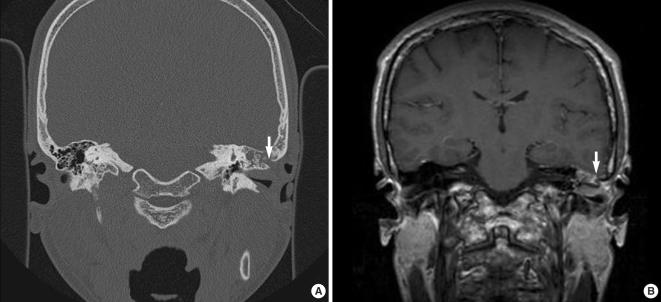

颞骨髓肉瘤。

Temporal bone myeloid sarcoma.

Myeloid sarcoma is a rare condition that's caused by the aggregation of immature myeloid cells in leukemic patients. Myeloid sarcoma occurring in the temporal bone more frequently involves the mastoid bone than is the case for metastatic lesions arising from non-systemic malignancies. The disease is difficult to diagnose when it presents with symptoms that mimic otomastoiditis. However, an early diagnosis is important in order to achieve complete remission of the disease. Magnetic resonance imaging of the temporal bone is useful for making the diagnosis of myeloid sarcoma, and especially to evaluate the extent of disease. High-dose radio- or chemotherapies are the first-line approaches and possibly the only approaches to achieve complete remission and to cure the disease. With the aim of improving our understanding of myeloid sarcoma in the temporal bone, the present report describes our experience with 5 such cases and we compare the clinical features of these 5 patients with those clinical features of patients who have metastatic lesions.

骨髓肉瘤是一种罕见的病症,由白血病患者中未成熟髓细胞的聚集引起。发生在颞骨的骨髓肉瘤比非系统性恶性肿瘤转移病变更常累及乳突骨。当疾病表现出类似于乳突炎的症状时,诊断较为困难。然而,早期诊断对于实现疾病的完全缓解非常重要。颞骨磁共振成像有助于诊断骨髓肉瘤,特别是评估疾病的范围。高剂量的放化疗是一线治疗方法,可能是实现完全缓解和治愈疾病的唯一方法。为了提高我们对颞骨骨髓肉瘤的认识,本报告描述了我们对 5 例此类病例的经验,并将这 5 例患者的临床特征与患有转移病变的患者的临床特征进行了比较。